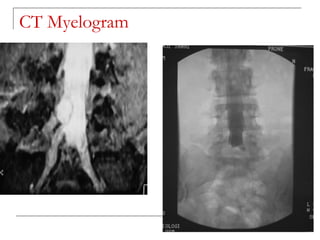

CT myelogram

   role replaced by MRI

   for delineation of neural structures where MRI

is not available/contraindicated

CT myelogram  role replaced by MRI  for delineation of neural structures where MRI is not available/contraindicated